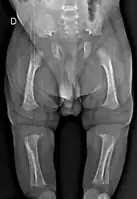

A skeletal survey is useful to confirm the diagnosis of achondroplasia. The skull is large, with a narrow foramen magnum, and relatively small skull base. The vertebral bodies are short and flattened with relatively large intervertebral disk height, and there is congenitally narrowed spinal canal. The iliac wings are small and squared, with a narrow sciatic notch and horizontal acetabular roof.[15][16] The tubular bones are short and thick with metaphyseal cupping and flaring and irregular growth plates.[15] Fibular overgrowth is present. The hand is broad with short metacarpals and phalanges, and a trident configuration. The ribs are short with cupped anterior ends.[15] If the radiographic features are not classic, a search for a different diagnosis should be entertained. Because of the extremely deformed bone structure, people with achondroplasia are often "double jointed". The diagnosis can be made by fetal ultrasound by progressive discordance between the femur length and biparietal diameter by age. The trident hand configuration can be seen if the fingers are fully extended.